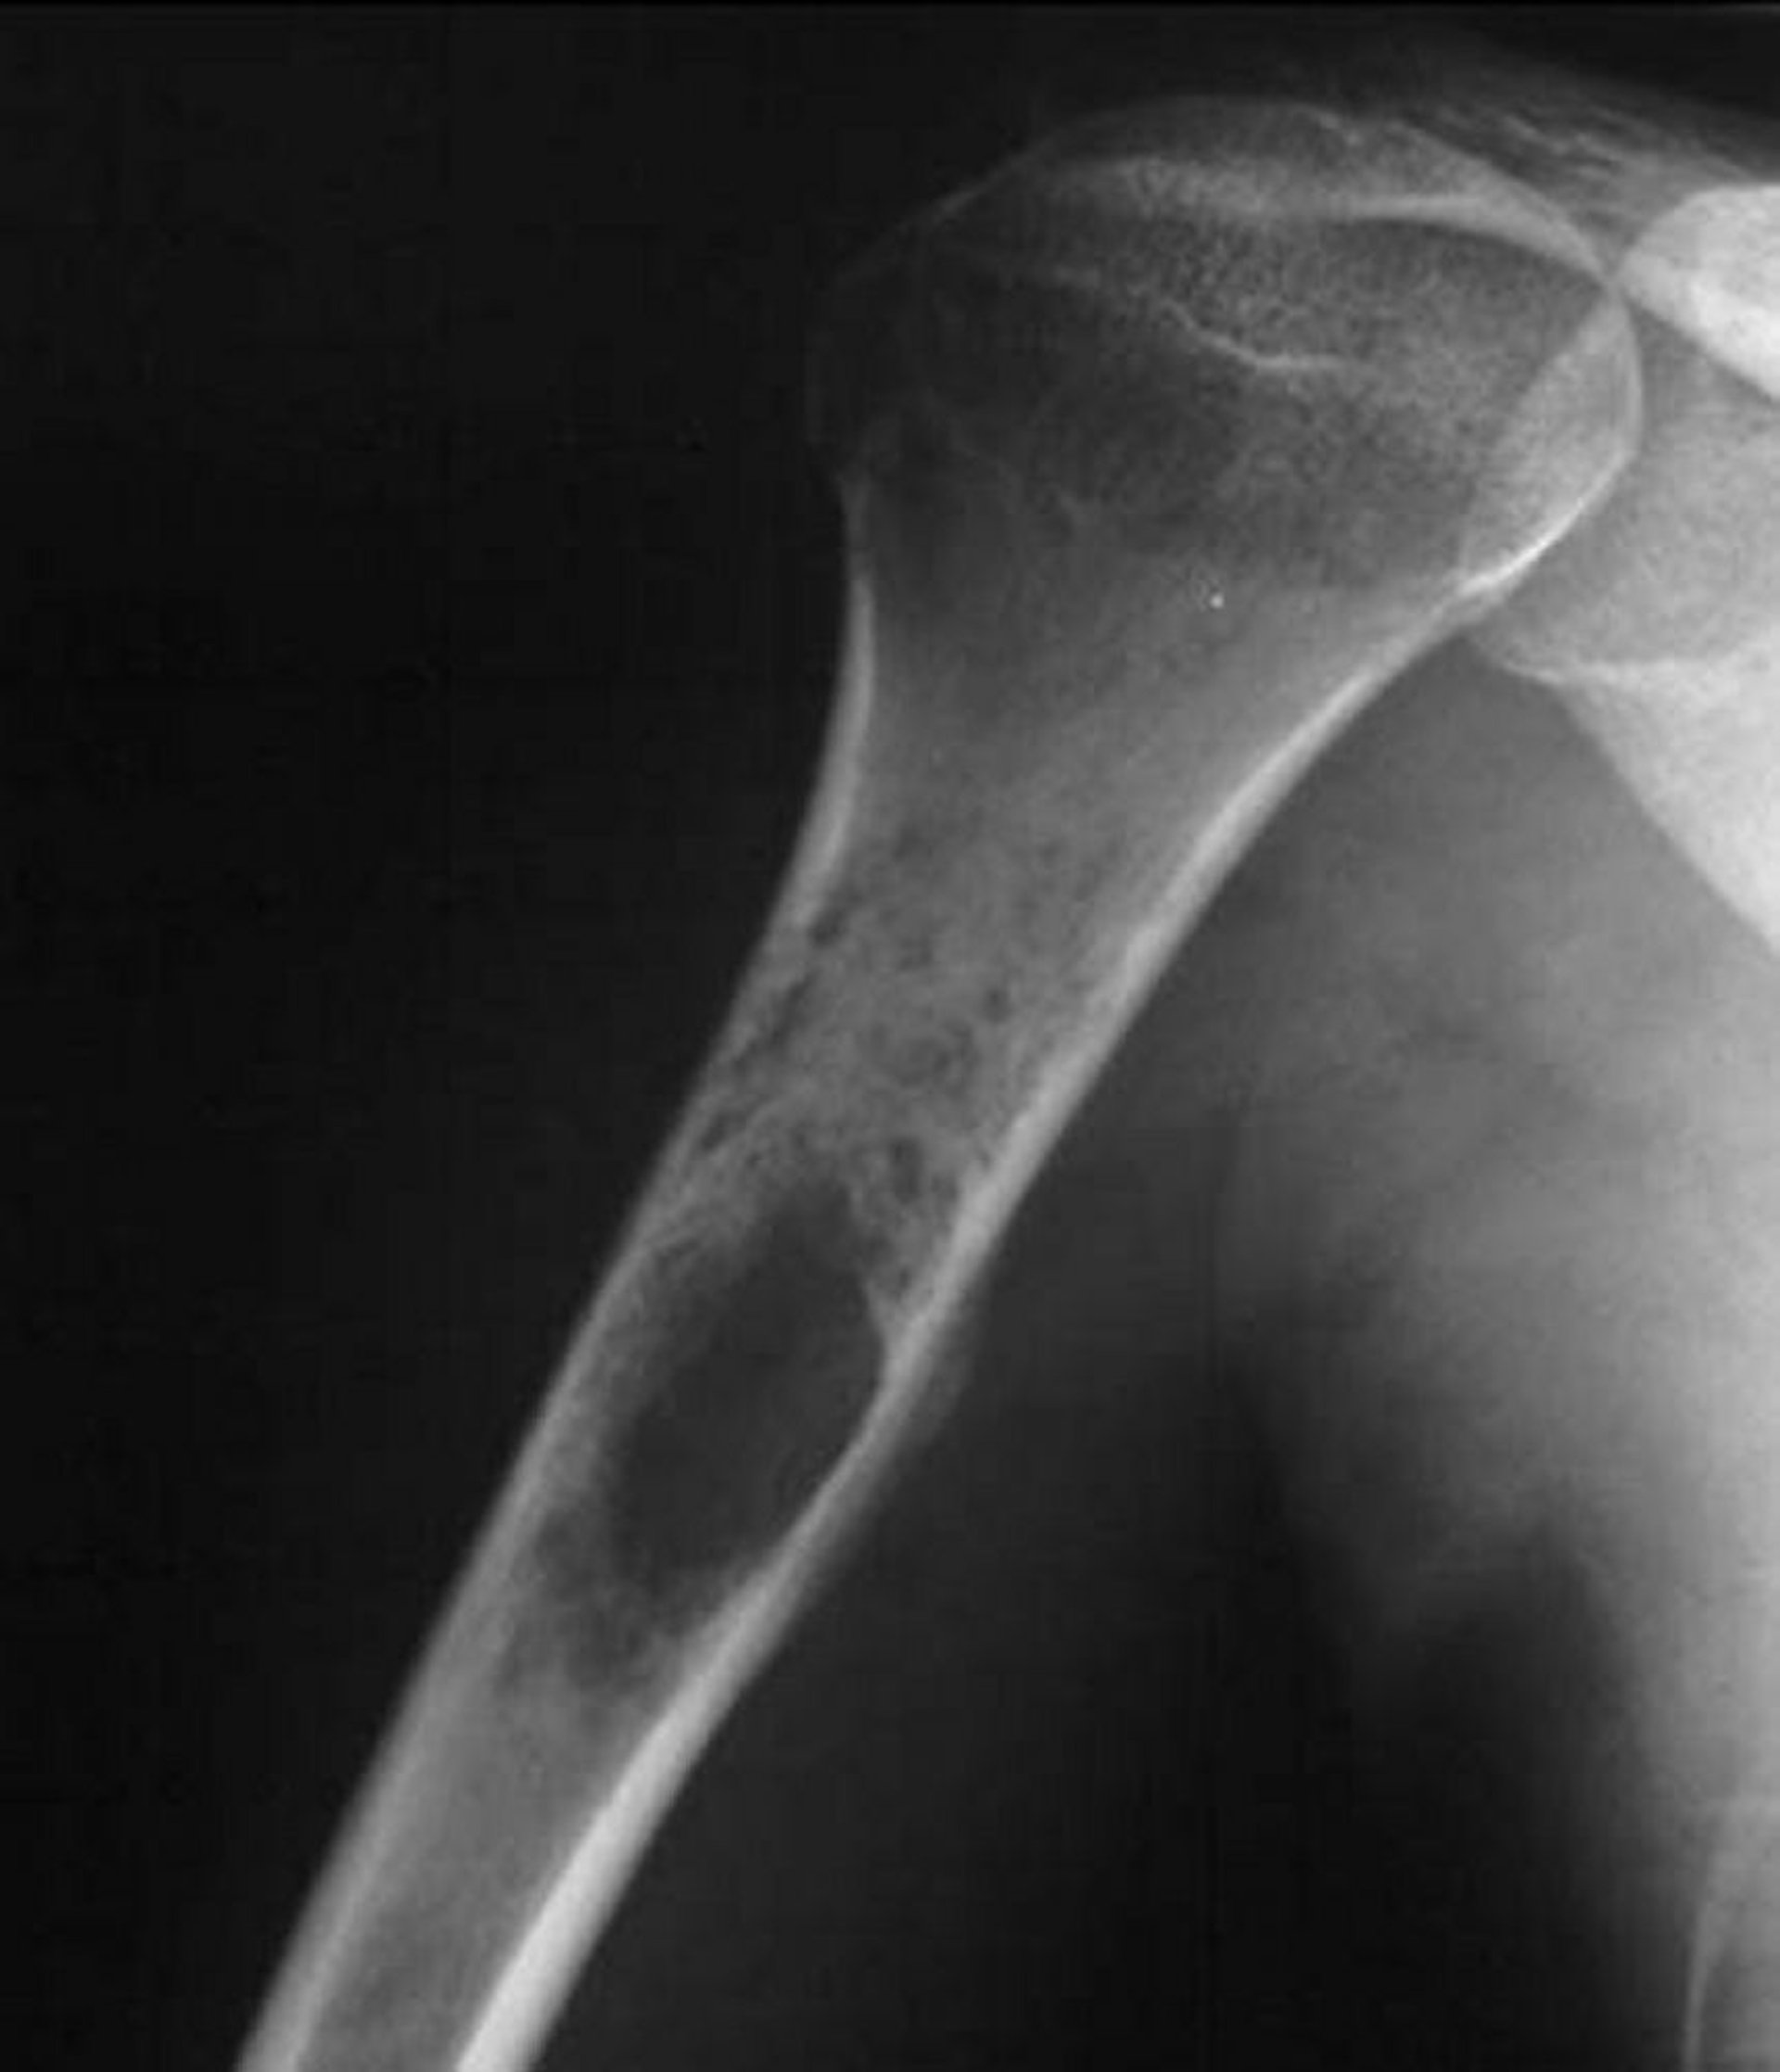

Sarcome d'Ewing de l'os

Cette radiographie de l'épaule montre une tumeur destructrice perméative naissant dans l'humérus proximal, ce qui est typique du sarcome d'Ewing.

Image courtoisie de Michael J. Joyce, MD, and Hakan Ilaslan, MD.